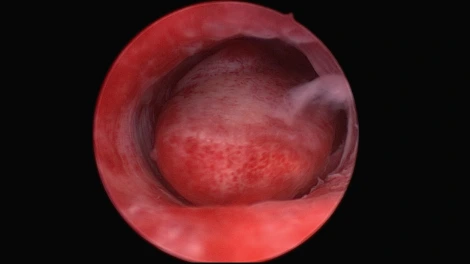

자궁경으로 확인한 자궁 내부에 위치하는 병변

진단을 위한 자궁경은 입원/마취 없이도 시술을 진행할 수도 있으나, 자궁경 수술을 통해서 자궁근종을 제거하기 위해서는 입원/마취가 필요합니다. 자궁경 수술 전에 자궁 입구(자궁경부)를 넓혀주는 약을 사용하거나, 기구를 삽입하기 위해서 입원이 필요하며, 원활한 수술 진행과 심한 통증의 조절을 위해서 마취가 필요합니다.